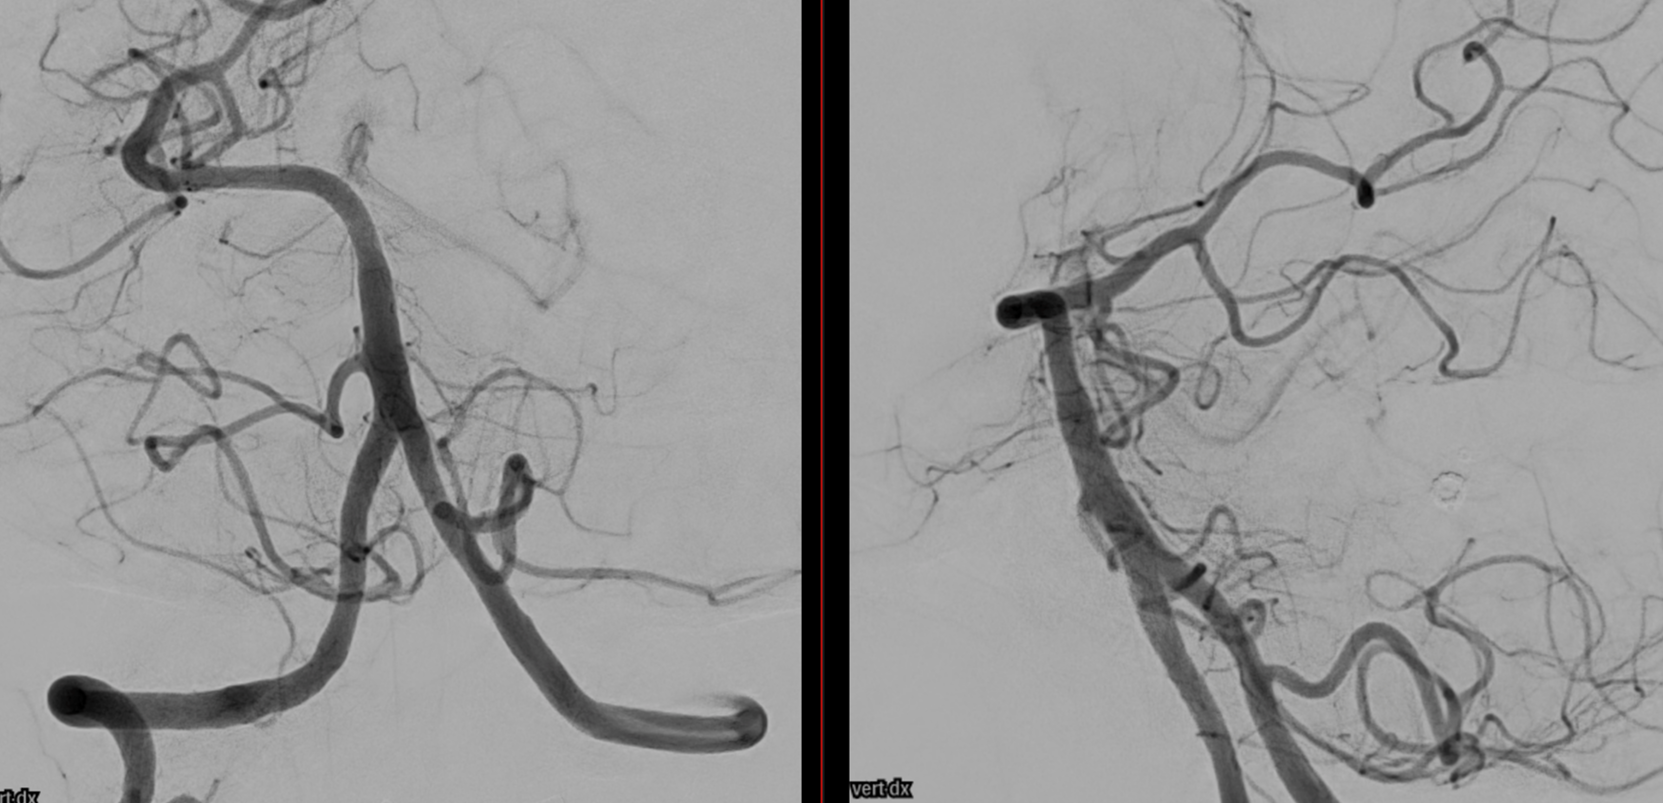

Wide neck MCA trifurcation aneurysm.

Y stenting with Atlas and Lvis Evo, in emergency. The Atlas diameter was too large because of the temporary limited availability in our centre; we can clearly see the struts of the Atlas too open at the level of the aneurysm neck (arrow). Even the microcatheter for coiling is fully visible jailed by the Lvis Evo in M1

The injection of contrast medium (250 mg/ml, 50% dilution, manual injection, same reconstruction protocol as previous images) reduces the visibility of the struts — an important point to consider. Not everything is always the same contrast dilution, same injection rate, etc. etc. — you need to know how to vary every parameter to achieve desired results.